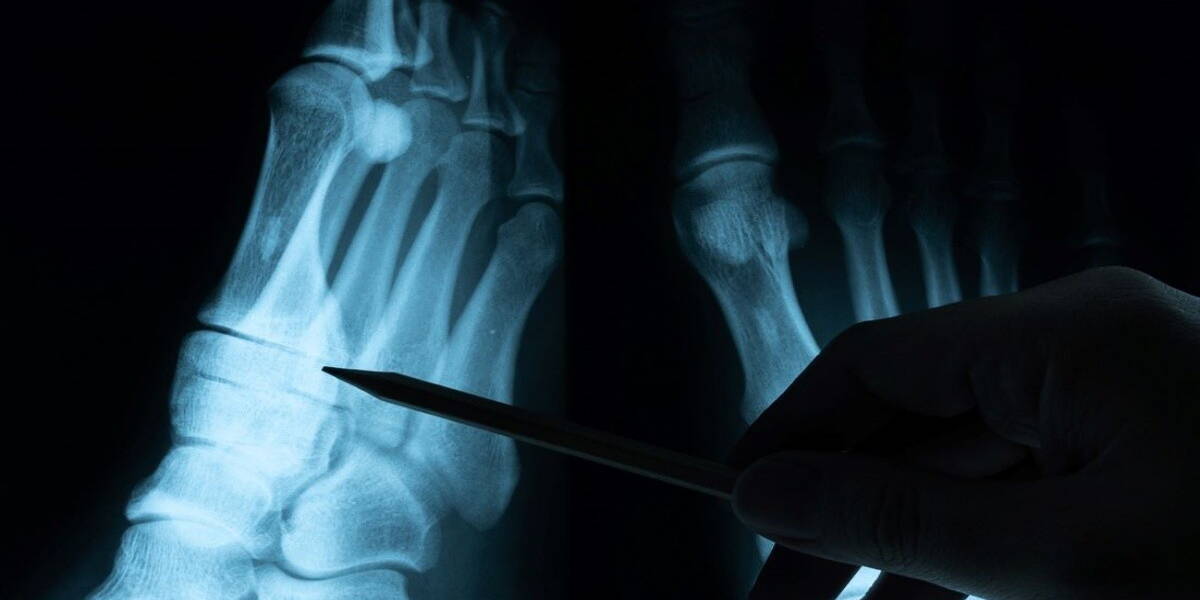

Zuyderland is volgens betrokkenen het eerste ziekenhuis dat een vorm van thuismonitoring inzet bij eenvoudige letsels. Patiënten hoeven daardoor niet meer standaard naar het ziekenhuis te komen voor een controle. Ze kunnen met het thuismeten programma ´eenvoudige botbreuken en eerste ontwrichtingen´ aan zelfmanagement doen. Wanneer het minder goed gaat is er een e-nurse beschikbaar en ook kan, indien nodig, altijd nog een fysieke afspraak worden gemaakt. Naar verwachting kunnen met dit initiatief zo’n duizend poliklinische controles per jaar worden voorkomen in Zuyderland.

In de Thuismeten app, die de patiënt op zijn of haar telefoon installeert, vindt de patiënt informatie over eenvoudige letsels. Tevens kunnen  video’s met oefeningen worden bekeken. De patiënt beantwoordt in week één, drie en zes steeds één vraag over de vordering van zijn of haar herstel. Hier volgt automatische berichtgeving op. Door gebruik te maken van de thuismeten app (Luscii) kunnen fysieke controle-afspraken voorkomen worden. Ook heeft de patiënt meer gedetailleerde informatie en regie over het herstelproces dan voorheen. Naar verwachting kunnen met dit initiatief zo’n duizend poliklinische controles per jaar worden voorkomen in Zuyderland.

Er zijn inmiddels al meer digitale initiatieven op de markt, die kunnen helpen dat mensen met eenvoudige letsels onnodig vaak naar het ziekenhuis hoeven te komen. Een andere optie bij eenvoudige letsels is bijvoorbeeld de zogeheten Virtual Fracture Care-app, die al in meerdere ziekenhuizen standaard wordt gebruikt. Met deze app wordt onder meer voorkomen dat patiënten met eenvoudige botbreuken fysiek naar het ziekenhuis moeten komen voor nacontrole. Tevens biedt de app thuis ondersteuning met heldere behandelplannen en oefeningen. Deze app is. net als de nieuwe Thuismeten app van Zuyderland gericht op zoveel mogelijk zelfmanagement en het terugdringen van het aantal poliklinische bezoeken.